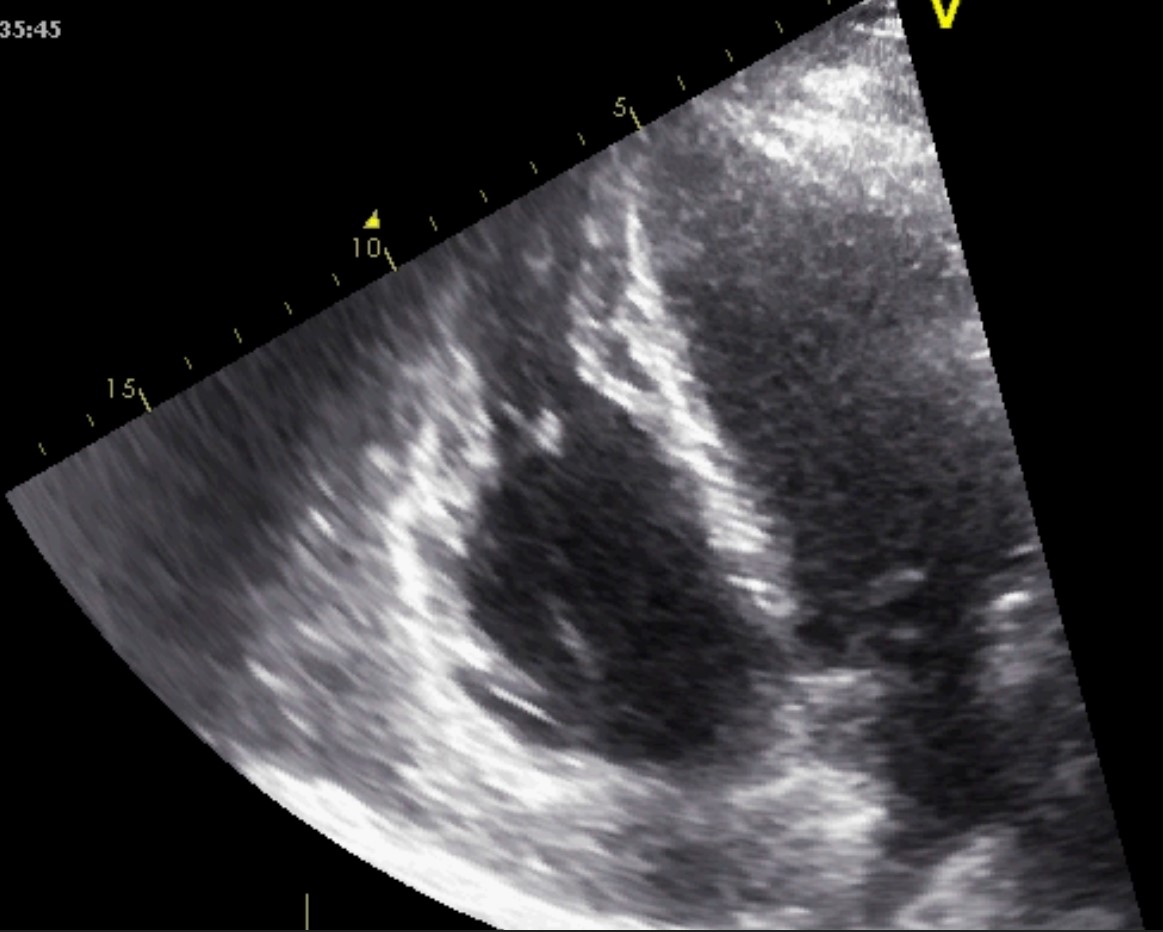

Restrictive cardiomyopathy (RCM) is characterized by non-dilated ventricles, mild or no myocardial hypertrophy with impaired ventricular filling, thus it is defined by abnormal ventricular diastolic function with a normal size LV (see Fig. 8). In the early stages of the disease, the systolic function of the LV is also normal [38].

Fig. 8.The echocardiographic aspect of RCM in an elderly patient presenting with signs and symptoms of heart failure. Apical 4 chamber view showing severe biatrial enlargement, with left atrial thrombus and non-dilated left and right ventricles.